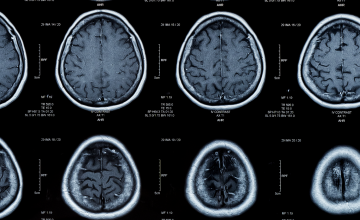

Diagnosis for Alzheimer’s disease using CSF samples allows the detection of four proteins: two forms of amyloid (Aβ1-42 and Aβ1-40) proteins and two forms of Tau (Total Tau and phospho-Tau) proteins. If a patient has Alzheimer’s disease, then these proteins will be present in abnormally low (Aβ1-42 and Aβ1-42/Aβ1-40 ratio) and high (Total Tau and phospho-Tau) levels. The Aβ1-42 levels and the Aβ1-42/Aβ1-40 ratio will even be low long before the symptoms of the disease start to show.